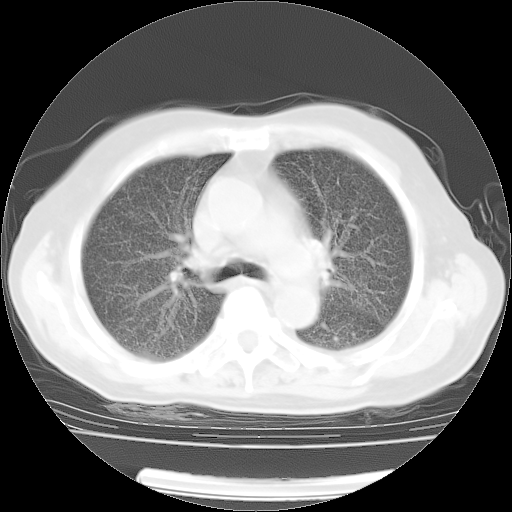

4月14日肺部CT

肺部CT平扫未见异常。